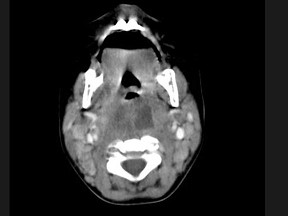

[多选题] 10个月大的婴儿,发热,曾患中耳炎,CT扫描如图所示,正确的描述或诊断是()A . 咽后壁软组织肿胀B . 其内密度不均C . 颈椎骨质未见明显异常D . 咽后壁脓肿E . 咽后壁寒性脓肿